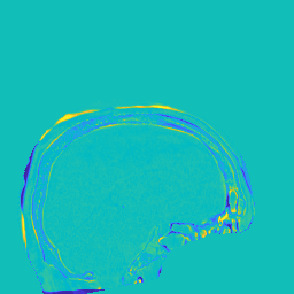

Model-based treatment planning for transcranial ultrasound therapy typically involves mapping the acoustic properties of the skull from an x-ray computed tomography (CT) image of the head. Here, three methods for generating pseudo-CT images from magnetic resonance (MR) images were compared as an alternative to CT. A convolutional neural network (U-Net) was trained on paired MR-CT images to generate pseudo-CT images from either T1-weighted or zero-echo time (ZTE) MR images (denoted tCT and zCT, respectively). A direct mapping from ZTE to pseudo-CT was also implemented (denoted cCT). When comparing the pseudo-CT and ground truth CT images for the test set, the mean absolute error was 133, 83, and 145 Hounsfield units (HU) across the whole head, and 398, 222, and 336 HU within the skull for the tCT, zCT, and cCT images, respectively. Ultrasound simulations were also performed using the generated pseudo-CT images and compared to simulations based on CT. An annular array transducer was used targeting the visual or motor cortex. The mean differences in the simulated focal pressure, focal position, and focal volume were 9.9%, 1.5 mm, and 15.1% for simulations based on the tCT images, 5.7%, 0.6 mm, and 5.7% for the zCT, and 6.7%, 0.9 mm, and 12.1% for the cCT. The improved results for images mapped from ZTE highlight the advantage of using imaging sequences which improve contrast of the skull bone. Overall, these results demonstrate that acoustic simulations based on MR images can give comparable accuracy to those based on CT.